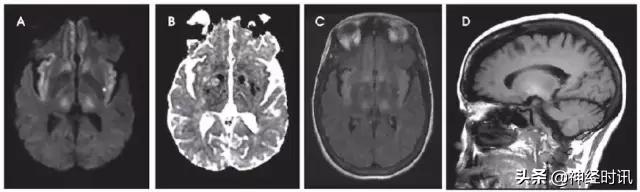

东部马脑炎

这是一种蚊子传播的虫媒病毒,临床表现可从感冒样症状、意识模糊和嗜睡,到神经功能缺损、癫痫发作和昏迷。约5%感染导致脑炎,1/3患者死亡,存活患者遗留明显残疾。典型病灶出现在双侧基底节、丘脑和脑干T2-FLAIR高信号(图11)。皮层和脑室旁白质受累相对少见。

图11 一例43岁男性,发热、头痛、精神状态改变2天,发病2天前曾野营。入院MRI显示双侧基底节、丘脑和岛叶T2-FLAIR(A)高信号和轻度弥散减低(B:DWI,C:ADC),左侧重于右侧。数天后MRI显示更为广泛的基底节和岛叶皮层受累(D:FLAIR)。